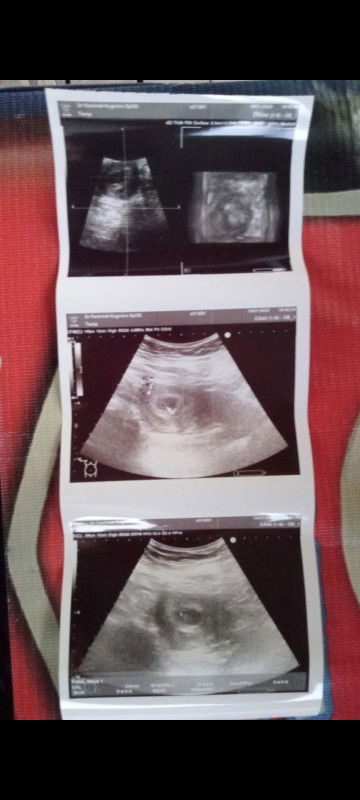

Mau tanya bunda saya klo menurut hpht 4 Desember 2022 itu di aplikasi usia kehamilan saya 7 wekk 3 hri . Tapi kmren sya USG tgl 19 Januari itu di USG 5 wekk 6 hri .dan alhamdulilah sdah kelihatan kantung dan janin nya Bun .itu kira2 normal gak ya Bun

USG usia di hasil USG 5minggu 6hari

Setelah di USG kantung janin nya sudah kelihatan dan janin nya . Detak jantung nya juga sdah ada .. Tapi itu apa ya maksudnya nya yg di gambar tengah ada bintik2 . Tolong ya semua